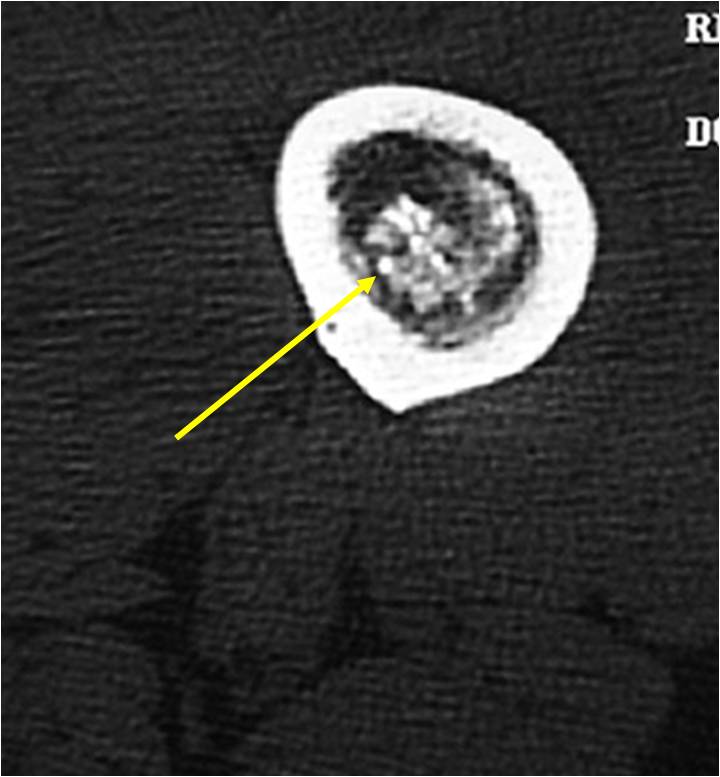

- Localized, radiolucent defect usually with punctate calcifications

- Calcifications are stippled, punctate, popcorn like calcifications and “Ring and Arc” calcifications

- Chondroid matrix with calcifications in majority of tumors

- There should never be any cortical destruction nor a soft tissue component. If this exists then the tumor must be a chondrosarcoma.

- Endosteal scalloping and cortical expansion is acceptable for phalangeal tumors. In most benign long bone cartilage tumors there is minimal endosteal scalloping but there should be no cortical expansion nor thickening. There should be no cortical destruction and no soft tissue component associated with an enchondroma. Cortical destruction, periosteal thickening, cortical expansion and a soft tissue component indicates a chondrosarcoma of the long bone.

- Cortical destruction and a soft tissue mass

- Periosteal reaction and thickening

- Endosteal erosion>2/3 cortical thickness on a CT scan